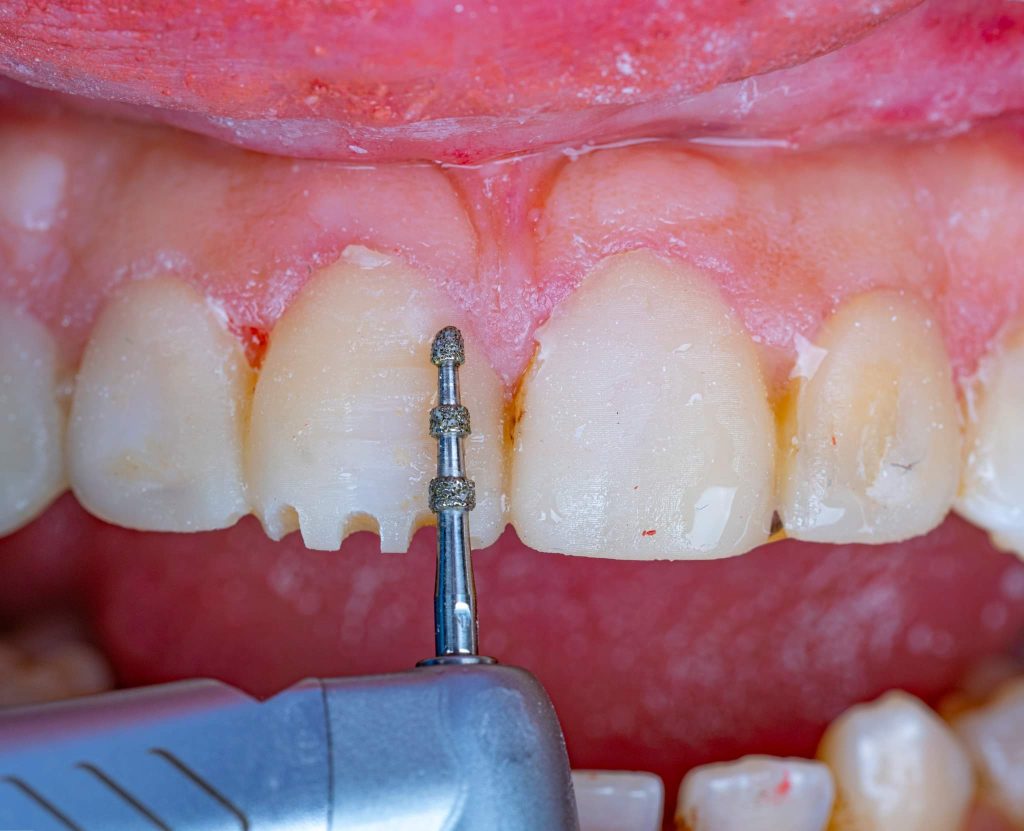

The case presented in this case report is for a 27-years-old female patient with a chief complaint of aesthetic correction for her smile. The patient was unhappy with her smile. After clinical examination, there were previous old composite veneering done poorly and incorrectly to close the multiple interdental spacing. After discussing the various treatment options (i.e., orthodontic treatment, direct, or indirect veneers), indirect ceramic veneering was selected. The step-by-step treatment protocol is presented in the images below.